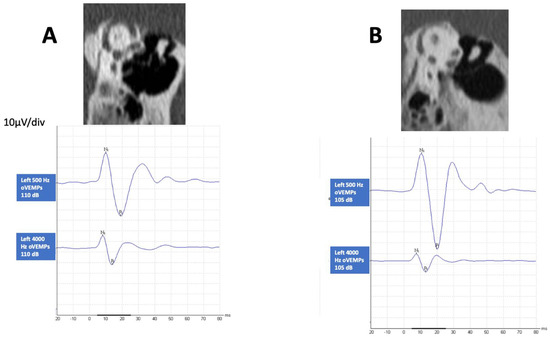

3.3. HFoVEMP

3.4. SVIN and HFoVEMP